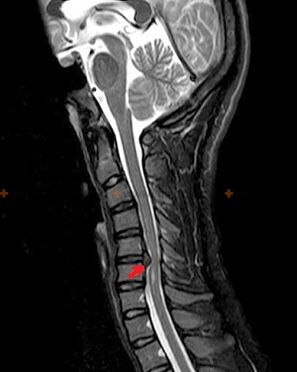

Diagnostics and radiographic signs

Osteochondrosis is a radiographic diagnosis, since a detailed clinical picture is available only at the time of exacerbation, while changes in the spine can occur with the complete subjective well-being of a person.Without an x-ray examination we can only speak of suspected osteochondrosis, because similar symptoms can be caused by other diseases (myositis, vertebral tumors and others).

To diagnose osteochondrosis, the following research methods are used: radiography (preferably with functional tests), MSCT and MRI.The latter study is preferable because it allows the state of the intervertebral structures to be visualized very clearly.

Radiographic signs of osteochondrosis include the following changes in the spine:

- Reduced height of the intervertebral discs.

- Presence of marginal bony growths.

- Violation of the position of the vertebrae relative to each other.

- Deformations of the bodies and vertebral arches, etc.

The presence of the changes described above, as well as changes in the structure of the intervertebral disc, detected by MSCT and MRI, serve as reliable signs confirming the presence of osteochondrosis.